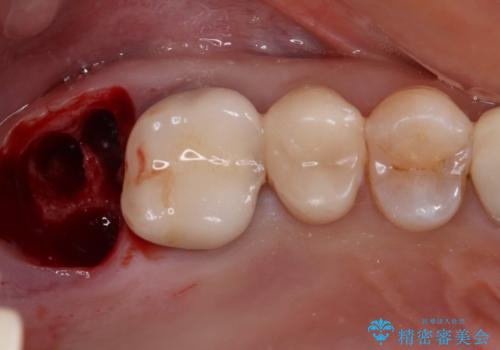

残念ながら歯冠から歯根に向かって破折が認められたため、患者様了解のもと、抜歯してインプラントの即時埋入を行いました。

インプラントと骨の安定程度を測定したところ、十分な数値が得られたため、速やかに仮歯を装着して咬合回復をさせることができました。

抜歯を含めた外科処置を1回に抑えることができ、あっという間に治療を終えることができました。